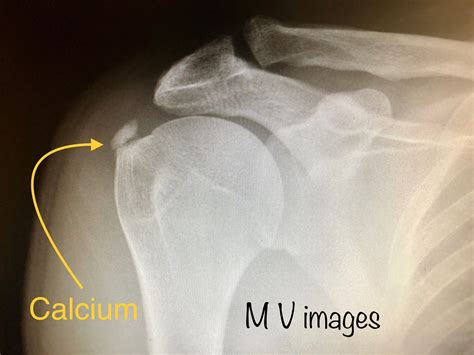

To confirm the diagnosis of calcium deposits in shoulder, an orthopedic specialist will usually conduct a physical examination followed by imaging tests. Because these deposits are essentially mineral structures, they show up very clearly on standard medical imaging.

X-ray The most common tool; clearly shows the shape and size of the calcium deposit.